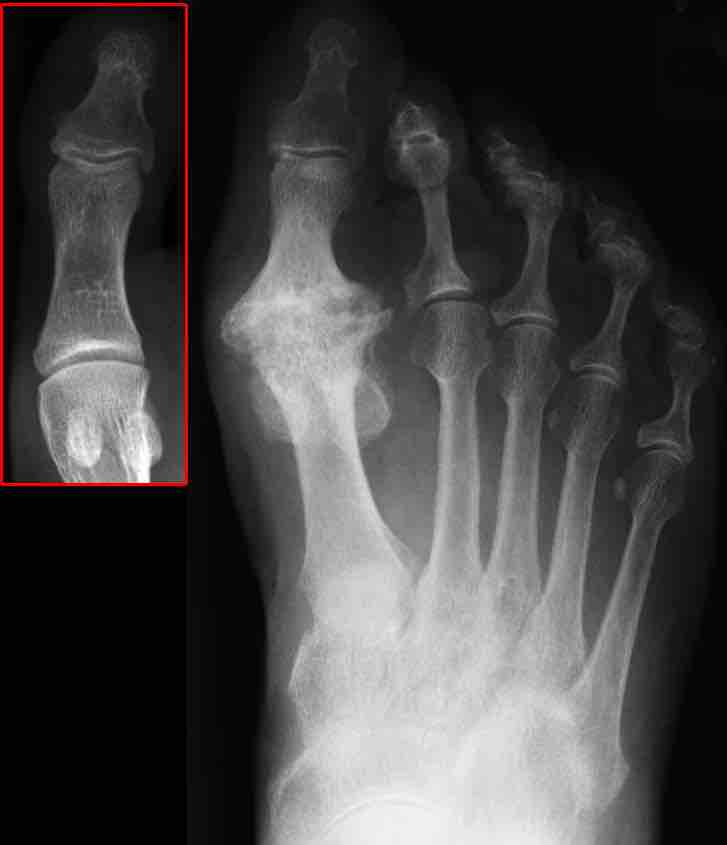

X-ray image of osteoarthritis of the big toe. The red box shows the normal joint.